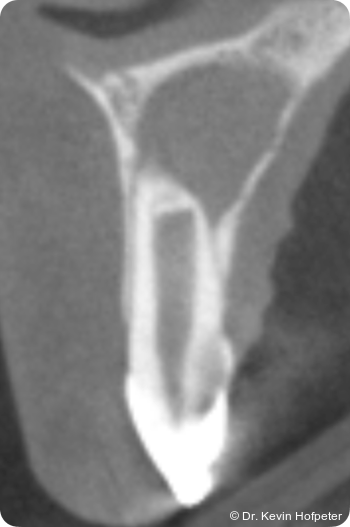

Zwei Monate später konnte die definitive Obturation erfolgen. Da der Kanal nun trocken war, konnte die Dentinbrücke im apikalen Bereich unter Sicht entfernt werden (Abb. 3). Das Mineral Trioxid Aggregat (MTA, Medcem) wurde frisch mit steriler Kochsalzlösung angemischt und mithilfe einer MTA-Gun (MAP-System, Produits Dentaires) sowie individuell angepassten Guttaperchastiften in den gekrümmten Kanalabschnitt eingebracht. Die größte technische Herausforderung bestand im Einbringen eines dichten apikalen MTA-Verschlusses hinter der Kurvatur (Abb. 4). Nachdem dieser Verschluss gesetzt war, wurde der restliche Kanal mit einem Epoxidharz-Sealer (AH Plus, Dentsply Sirona) und erwärmter Guttapercha mittels warm-vertikaler Kompaktion gefüllt und der Zugang adhäsiv verschlossen (Abb. 5).